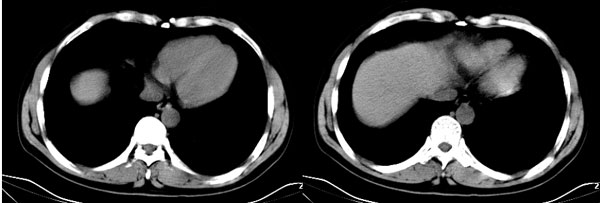

李**,男,46岁,便血1天入院,慢性贫血貌,腹平、软,剑突下压痛,肠鸣音稍活跃,hb大于1g/l,胃镜:慢性浅表性胃炎,b超:1肝内多发性占位 2腹腔内囊性肿块 ,肝内圆形影平扫ct值42.9,动脉期48.6,静脉期58.2,延迟期62.2

影像学表现:1 腹腔前中部、胰腺前方囊实性病灶(个人认为确定有否实性成分存在这是关键,涉及到鉴别诊断,如果是口服阳性造影剂则可明确左侧是不是小肠了),囊性部分囊壁不均,实性部分有强化,与小肠关系较密切,局部小肠受推移;与胰头、胃后壁均有脂肪间隙存在;2 胰腺无异常改变,胰周无渗出;3肝后段包膜下2个小圆形低密度灶,从图像和楼主提供的ct值来看有轻度强化,灶周无片状强化,不似单纯囊肿及肝癌、炎性病变表现;4 腹膜后及腹腔内无淋巴结肿大。

胰腺边界清晰,胰周筋膜不厚,胰周脂肪密度无明显增高;其前方囊实性病灶,边界清晰,增强后实性部分轻度强化;肝内多发边界清晰低密度影,增强后无明显强化(平扫ct值42.9,动脉期48.6,静脉期58.2,延迟期62.2)。